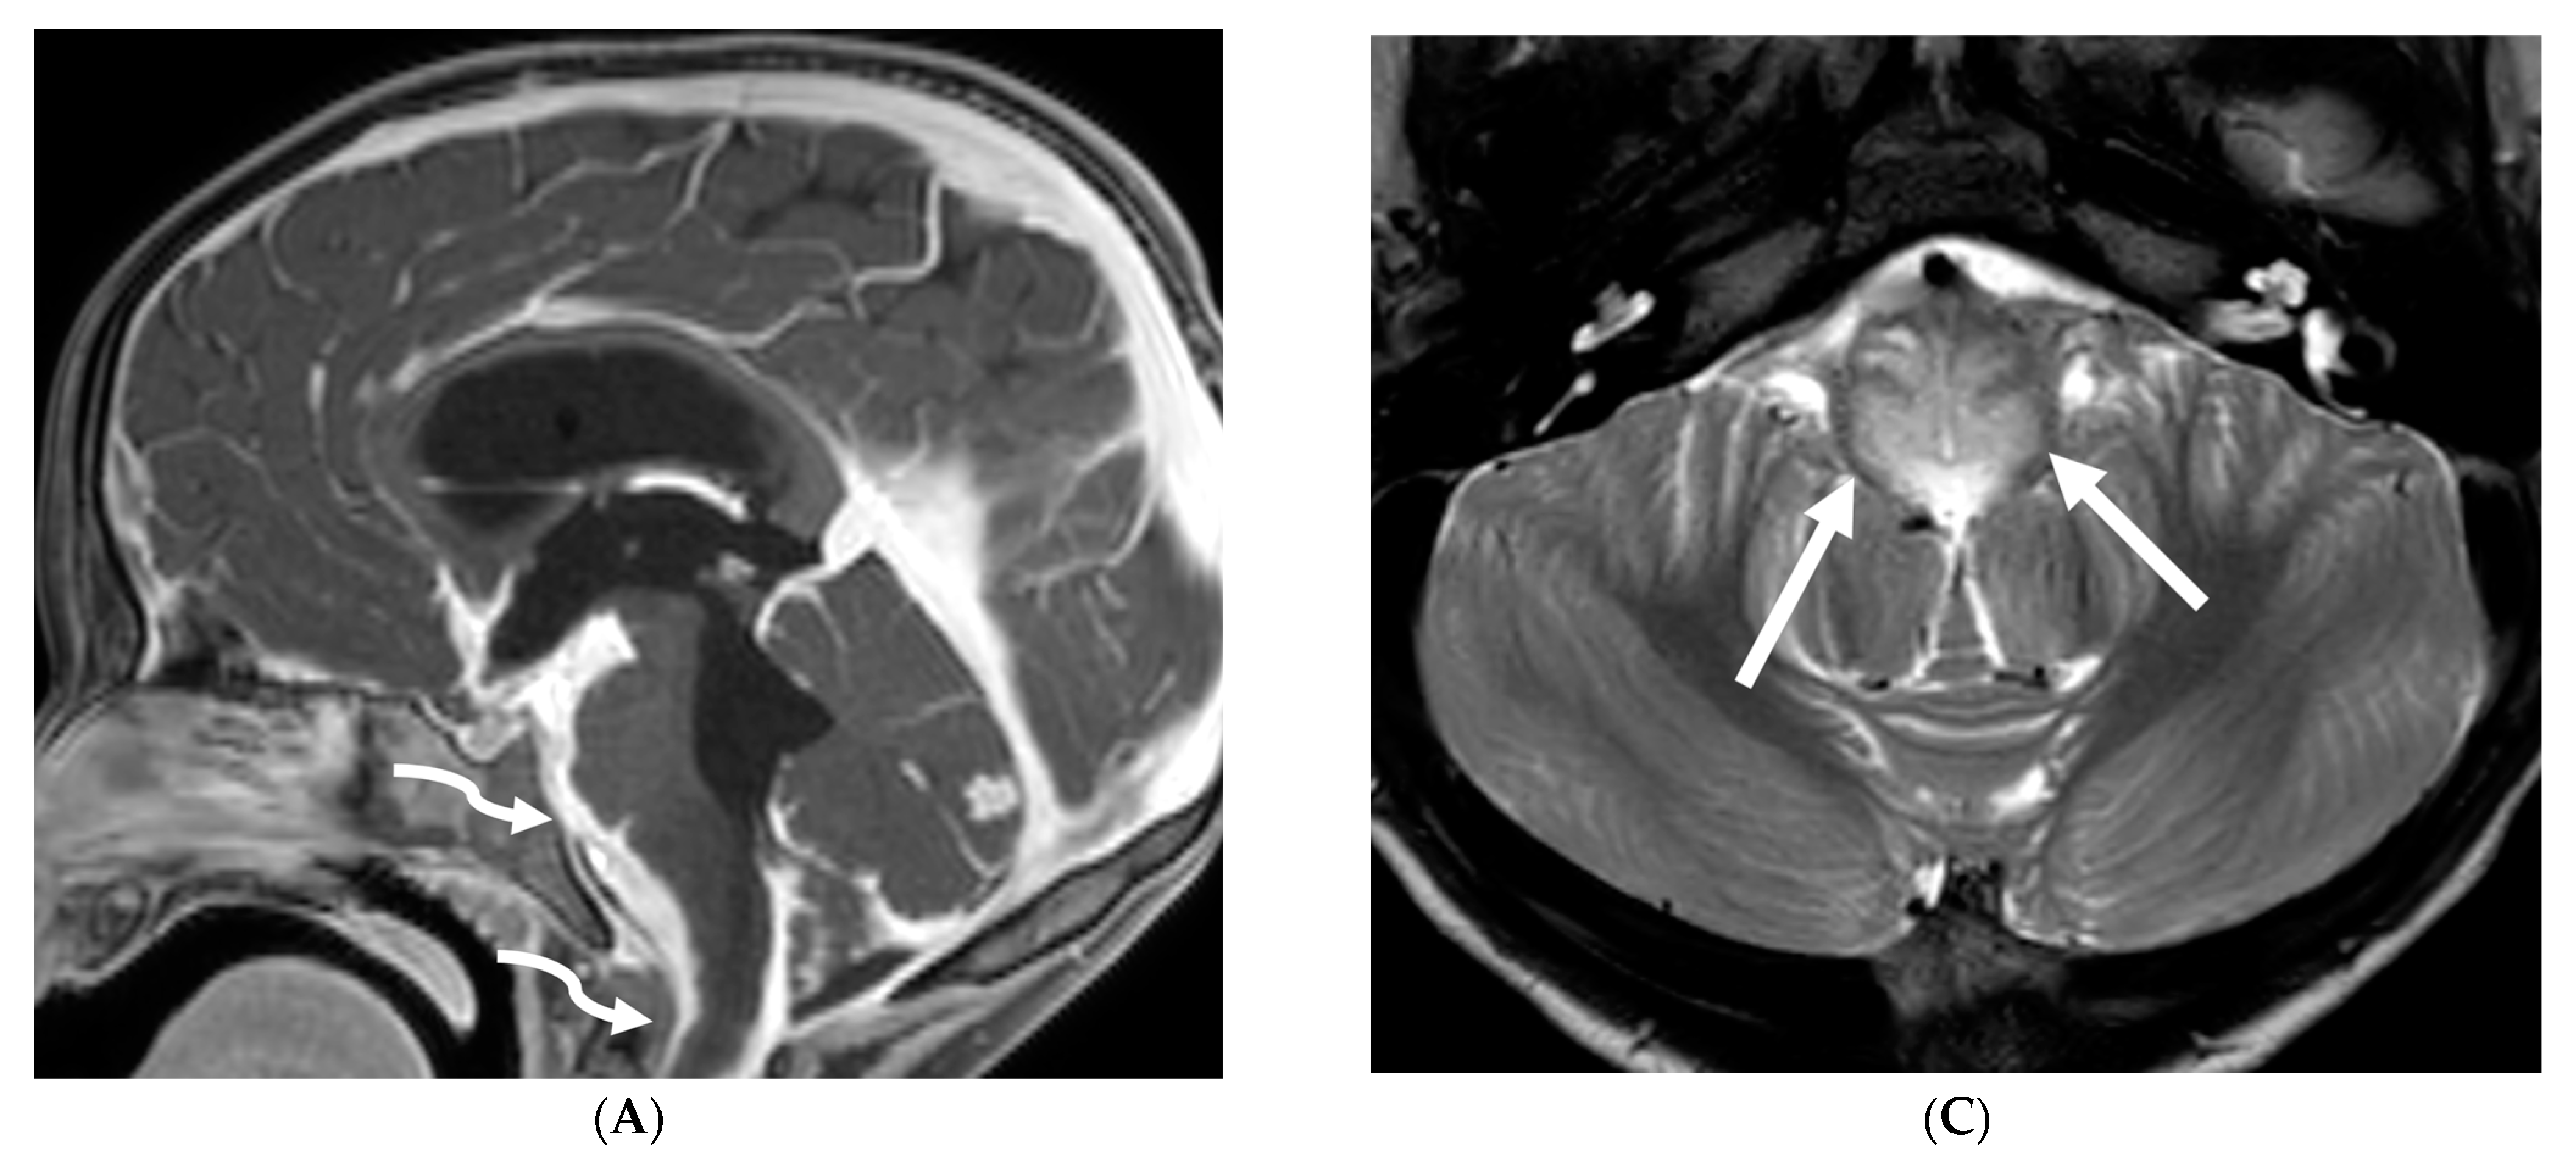

MRI features of IH can be explained by the Monroe-Kellie doctrine, which states that the intracerebral volume including blood, CSF and brain parenchyma remain the same. Thus, a decrease in CSF volume promotes dilatation and rounding of the venous sinuses, subdural fluid collections along with dural (pachymeningeal) enhancement which occurs due to vascular engorgement and transudation of fluid into it [67]. Hyperemia of the pituitary gland occurs which may mimic hyperplasia or pituitary tumor. Brainstem slumping or downward displacement of the brainstem, defined as red nuclei below the tentorium and low lying third ventricle below the sella, are highly specific indicators of IH, observed in half the cases. A pontomesencephalic angle of less than 50 degrees and mamillo pontine distance of less than 5.5 mm are sensitive and specific parameters to suggest IH [66].

With regard to spine imaging, in addition to the intracranial features of dural enhancement, venous engorgement and subdural collection, unique findings include meningeal diverticula, dural ectasia and C1–C2 sign (Figure 8 and Figure 9). Additionally, a CT myelogram may identify the precise location of the CSF leak which can be sealed off with a blood patch [65,68].

Figure 8.

Sagittal T1 (A), post axial T1 (B,C), axial CT myelogram (D) and technetium 99 m DTPA SPECT-CT (E): 16-year-old with Gorham’s disease. There is cerebellar tonsillar herniation and decrease in prepontine cisterns (white arrows). Significant increase in the size of the venous sinuses (dashed arrow). Diffuse pachymeningeal enhancement is seen (black arrows). Cystic-appearing foci at the skull base are in keeping with lymphangiomatosis with contrast pooling into the lytic lesion (curved arrow). Abnormal radiotracer extravasation in the left clival region correlating with lytic lesion (open arrow). Features are in keeping with intracranial hypotension secondary to CSF leak.

Figure 9.

Sagittal T2 FS (A), sagittal (B) and axial (C) T1 post contrast: 3-year-old with neck pain post LP. There is diffuse epidural thickening, with increased T2 signal and enhancement, throughout the cervical, thoracic and lumbar spine (white arrows). Several prominent flow voids are seen within the anterior epidural thickening in the upper cervical region (dashed arrow). There is also increased high T2 signal between the occiput and posterior arch of C1, and between the posterior arch of C1 and spinous process of C2 (curved arrows) in keeping with “C1–C2 sign”. Findings are related to intracranial hypotension post lumbar puncture.